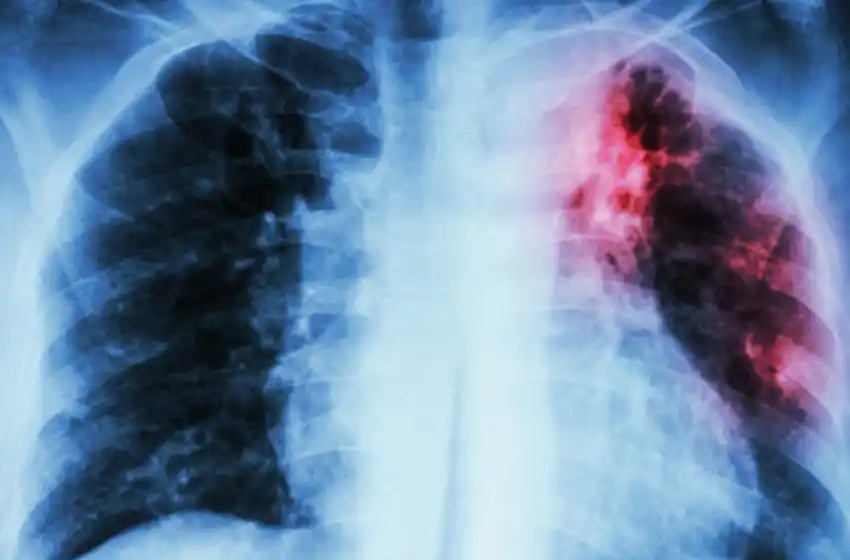

Se trata de una enfermedad infecciosa causada por Mycobacterium tuberculosis, una bacteria que casi siempre afecta a los pulmones y se transmite a través del aire. Si bien los síntomas son tos, dolor torácico, debilidad, pérdida de peso, fiebre y sudores nocturnos, en las personas sanas, los síntomas no suelen aparecer ya que el sistema inmunitario actúa para bloquear la bacteria.